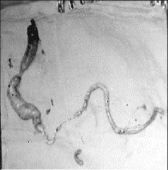

Se extendía desde la ingle hasta alcanzar las cavidades derechas del corazón

Resultó que la paciente tenía un tumor que nacía en la zona de la ingle izquierda y se extendía por la vena cava inferior hasta las cavidades derechas (aurícula y ventrículo) del corazón. Medía un metro 46 centímetros de largo, 3.5 centímetros de diámetro y un peso de 300 gramos.